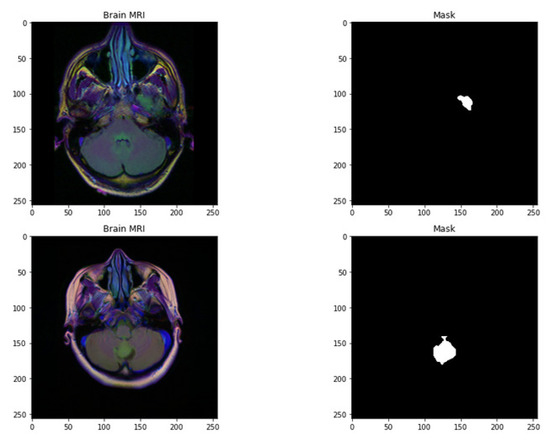

Figure 1.

Random sample images with their corresponding mask.

The dataset used in this work is collected from TCGA (The Cancer Genome Atlas) and TCIA (The Cancer Imaging Archive) [35,36]. The number of identified patients from a lower grade of malignant tumors of the nervous system of TCGA was 120. Individuals had preoperative imaging data, at least one containing an inversion recovery process with fluid attenuation. Ten patients were excluded from this dataset as they required informed consent regarding the available genomic constellation information. The final group that remained in this dataset consisted of the remaining 110 patients. A detailed list of patients has been provided in Online Resource 1. The remaining patients were divided into 22 separate, non-overlapping clusters. Each cluster contains five patients. The process was completed for the evaluation with a cross-validation technique. The imaging dataset used in our research work was captured from the Imaging Archive. Sample images are shown in Figure 1. This dataset consists of the patients’ images related to TCGA and is subsidized by the National Cancer Hospital. We used all the treatments when available, but when one was not, we only used FLAIR. Six patients lacked the pre-contrast sequence, nine lacked the post-contrast sequence, and 101 had all the relevant sequences. All of the patients’ information is published in Online Resource 1. Between 20 to 80 patients had the number of slices recorded. We only looked at bilateral data to determine the initial pattern of tumor progression. The genomic dataset used in this investigation included IDH mutation and DNA methylation measurements. We consider six previously discovered genetic classifications of LGG in our research, which are known to be connected with some aspects of tumor form.